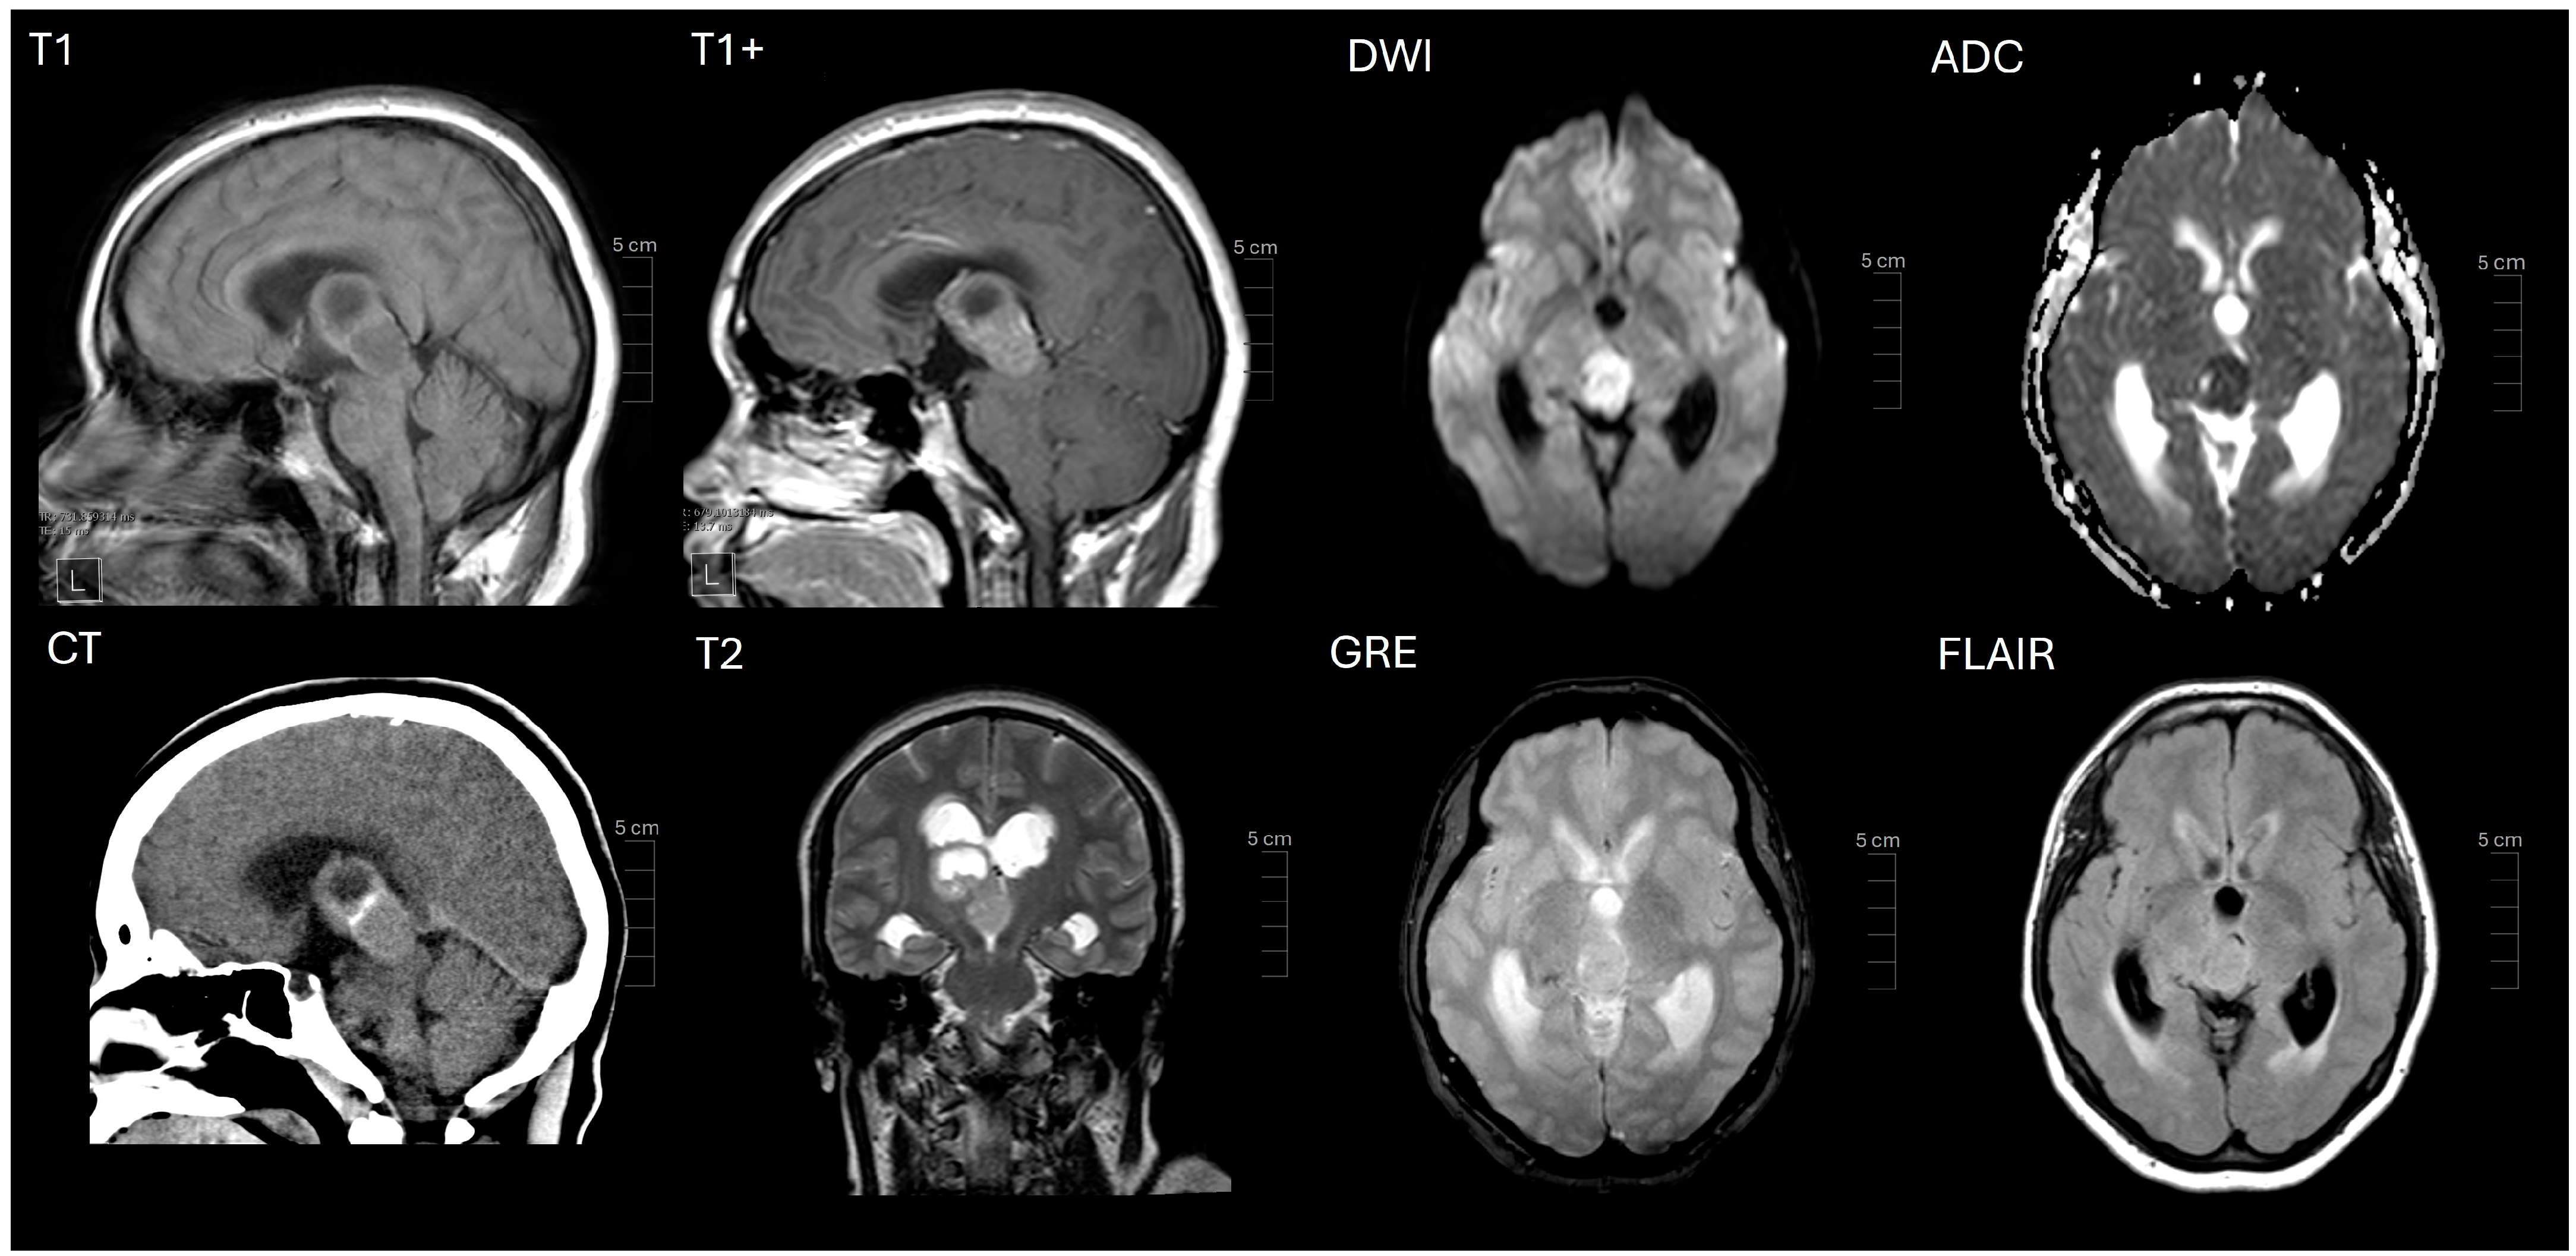

2. Case Presentation